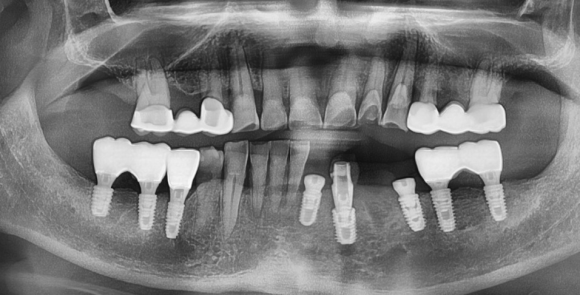

결국 4개 치아를 발치하여야 했지만..

환자분의 사람 만나는 모임 일정과 사정을 고려해

그나마 뼈가 괜찮고 발치 후 즉시임플란트 식립 치료가 가능한 송곳니 부터 임플란트를 심고,

당일에 머리까지 올려 드렸습니다.

남은 뼈가 그나마 단단하고 양이 많았기 때문에 가능하죠.